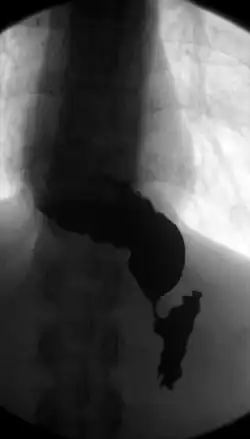

![]() R-контрастный снимок сульфатом бария, видны замедление поступления жидкости в полость желудка через суженный просвет сфинктера и скопление её в расширенном просвете пищевода S-образной формы | |

Кардиоспа́зм (от греч. ϰαρδία [kardia] «сердце», в данном случае подразумевается кардиальные отделы желудка и пищевода + спазм; в англ. achalasia cardia[1]), или ахалази́я ка́рдии, или ахалази́я пищево́да — хроническое нервно-мышечное заболевание, характеризующееся отсутствием или недостаточным рефлекторным расслаблением кардиального сфинктера, вследствие чего происходит функциональное (непостоянное) нарушение проходимости пищевода, вызванное сужением его отдела перед входом в желудок (кардии) и расширением вышерасположенных участков[2][3][4][5]. Развиваться может в любом возрасте.

| 4 стадия | Отмечается выраженное рубцовое сужение пищевода в сочетании с его расширением, S-образной деформаций и развитием осложнений - эзофагита и параэзофагита. |